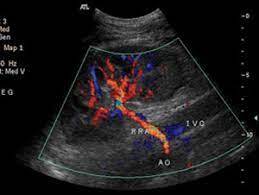

Estuda o fluxo nas artérias renais, desde sua origem na aorta abdominal até o rim, procurando identificar áreas de estenose (áreas onde o sangue para com mais dificuldade) nestes vasos. É Indicado para investigação de hipertensão arterial secundária, especialmente em pacientes jovens que podem estar com displasia fibrosa das artérias renais e investigação de doença aterosclerótica desses vasos em pacientes idosos.